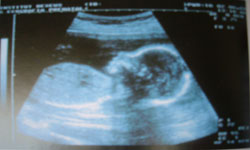

SEMANA 18 . TÚ... Aparece una línea oscura, la línea alba, del ombligo al pubis, sobre todo si eres morena. Y TÚ BEBE... Una ecografía de alta resolución puede revelar si es niña o niño. Sus huesos se están formando rápidamente.

SEMANA 20 . TÚ... Tu ombligo puede aplanarse y salirse hacia fuera hasta después del nacimiento. Y TÚ BEBE... Su tamaño se ha doblado desde la semana 13ª.Te harán una eco para detectar problemas anatómicos o morfológicos. |